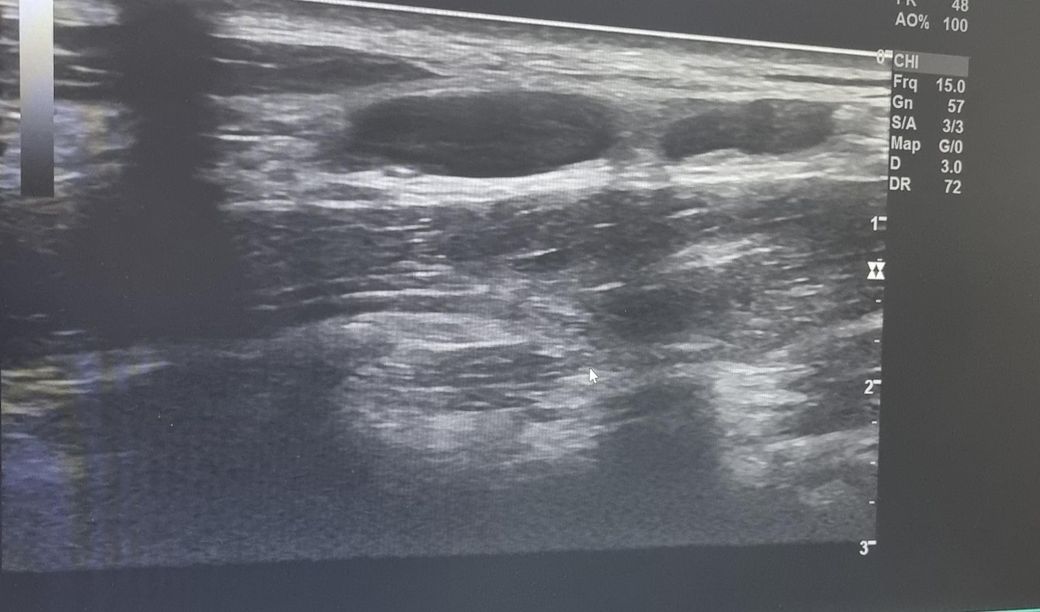

한 달 넘게 멍울 만져져서 초음파 받았는데 크기가 좀 커서요 괜찮나요? 궁금합니다 ㅜㅜ V5 구역입니다.

초음파 사진 괜찮나요 ㅜㅜ?